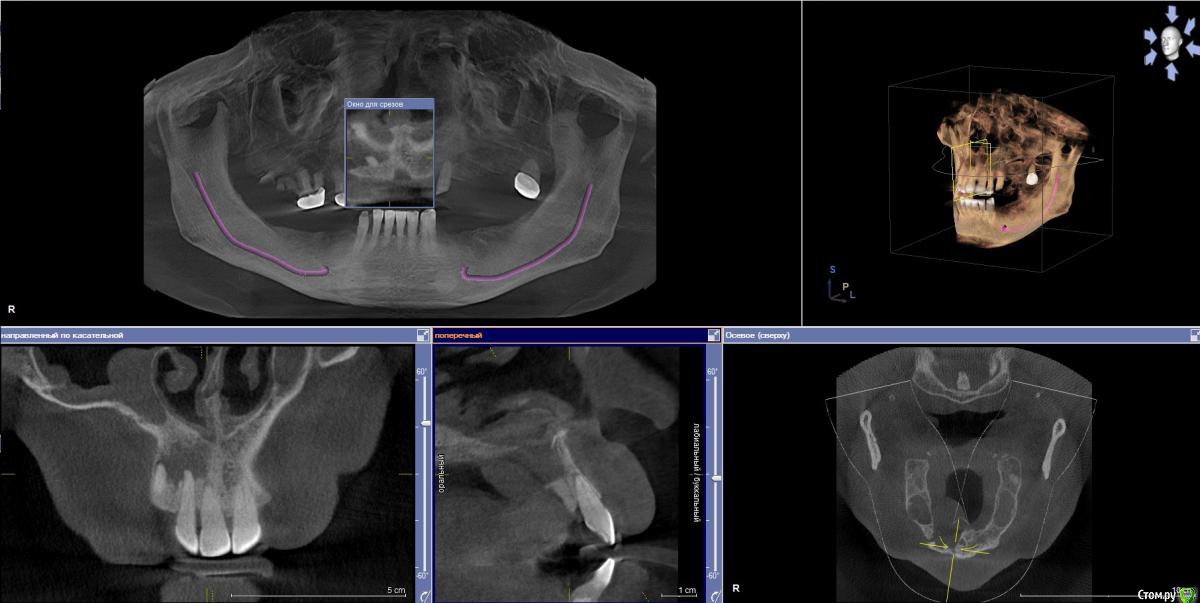

Doctormet Опубликовано 30 октября, 2015 Поделиться Опубликовано 30 октября, 2015 Доктора, приветствую! Нужна помощь в одном клиническом случае!Пациент обратился с целью протезирования. Жалоб на день осмотра не было. Замечал увеличивающееся образование в области неба в течение года. Осмотр: отмечается стираемость зубов передней группы на н\ч и в\ч примерно на 1 мм. Зубы 1.1, 1.2, 1.3 интактные, перкуссия безболезненная. В области твердого неба справа плотное безболезненное образование.Рентгенограмма: Разрежение включает верхушки корней 1.2, 1.3, 1.1, отсутствует латеральная стенка резцового канала, дно полости носа от 1.1 до 1.3 и небная стенка альвеолярного отростка от 1.1 до 1.5. Отмечается двустороннее затемнение верхнечелюстных пазух.Пациент заядлый курильщик. Травм в анамнезе не отмечает.В планах сдача анализов на гепатит, ВИЧ, сифилис, исключение сахарного диабета.Что можно предположить в данном случае? Связано ли данное образование с перегрузкой передних зубов, ЛОР патологией, либо же это киста носонебного канала или опухолевое образование?Снимки прилагаю. Спасибо! Ссылка на комментарий